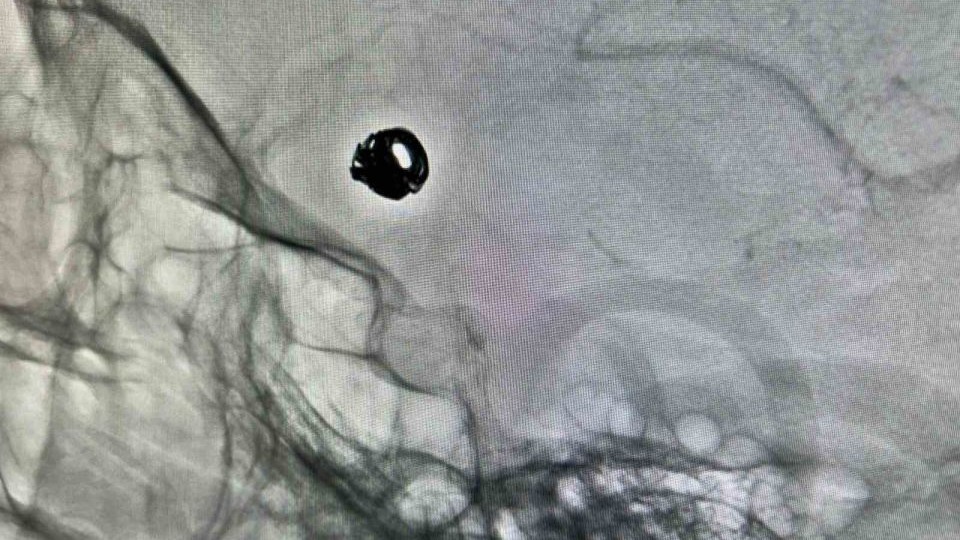

Bitlis Devlet Hastanesine bilinç bulanıklığı ve baş ağrısı şikâyetiyle başvuran 44 yaşındaki Sacide Derman, yapılan tetkiklerde beyin kanaması geçirdiği belirlenince ileri tedavi için Van Eğitim ve Araştırma Hastanesi’ne sevk edildi. Burada gerçekleştirilen anjiyografi sonucunda hastanın beyin damarlarında anevrizma (damar baloncuğu) tespit edildi. Girişimsel Radyoloji Merkezi’nde uygulanan kapalı anjiyografik yöntemle, kasıktan girilerek beyin damarlarına ulaşıldı ve anevrizma platin tel (coil) kullanılarak kapatıldı. İşlem sonrası takibi yapılan hastanın sağlık durumunun iyiye gittiği belirtildi.

Konuya ilişkin açıklama yapan Hastane Başhekimi Doç. Dr. Remzi Sarıkaya, her türlü komplike hastanın merkezlerine sevk edildiğini belirtti. Doç. Dr. Sarıkaya, "Hastamızın dış merkezde yapılan tomografi incelemesinde beyin kanaması ve beyin damarlarında anevrizma tespit edildi. Bunun üzerine hasta 112 ambulansı ile Van Eğitim ve Araştırma Hastanesi’ne sevk edildi. Kasıktan girilerek beyin damarlarına ulaşıldı ve endovasküler (kapalı yöntem) tedaviye uygun olduğuna karar verildi. Yaklaşık 1,5 saat süren işlemde, anevrizmanın içine platin teller (coil) yerleştirildi. Bu sayede baloncuğun kanla dolması engellenerek yeniden kanama ihtimali ortadan kaldırıldı" dedi.

"İlki bizim uyguladığımız kapalı yöntemdir. Bu yöntemde kasıktan girilerek beyin damarına ulaşılır, baloncuk platin telle kapatılır. İkincisi ise açık beyin ameliyatıdır. Bu yöntemde kafatası açılarak anevrizmanın boynuna klips adı verilen özel bir kıskaç yerleştirilir ve baloncuğun kanla dolması önlenir. Her iki yöntemde de amaç aynıdır; baloncuğu devre dışı bırakmak. Ancak kapalı yöntem, hasta açısından daha konforludur. Açık yara olmadığından komplikasyon riski daha düşüktür ve hastanede kalış süresi daha kısa olup hastalar daha kısa sürede günlük aktivitelerine dönebilmektedir. Hastamızı bir hafta önce işlem için almıştık. Şu anda durumu gayet iyi olup takibi ve ilaç tedavisi devam etmektedir."